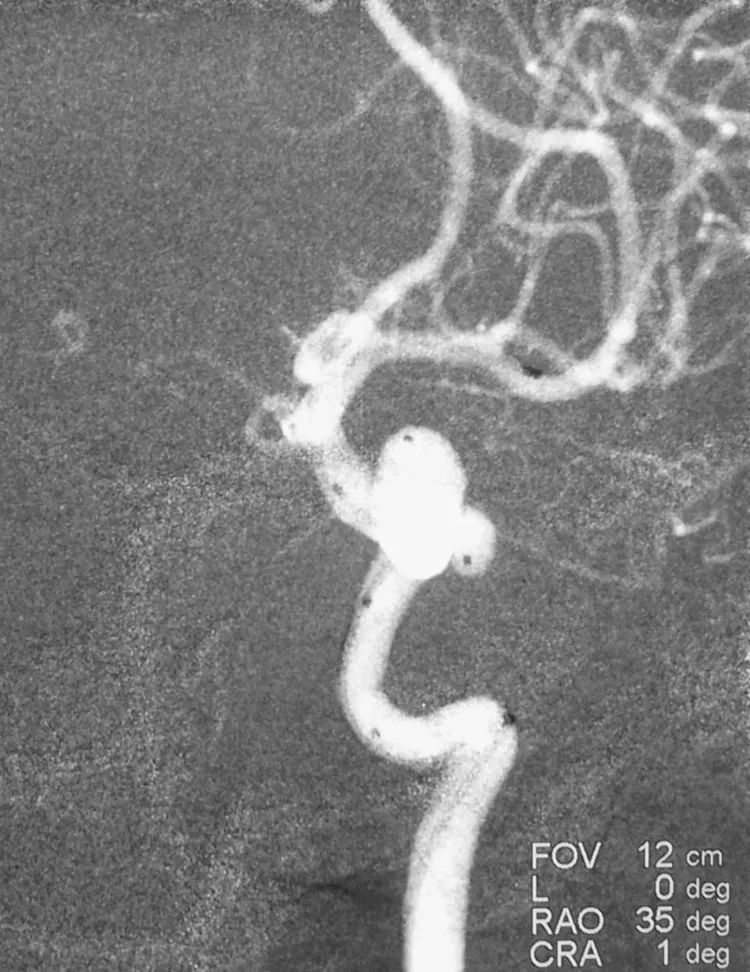

2019年3月13日行DSA+介入治疗。术前左颈内动脉造影三维重建显示左侧后交通动脉瘤,呈牛角形分叶;后交通动脉由瘤颈近心端发出,非胚胎性:

测量,公共瘤颈宽5.40 mm,大分叶4.86 mm×6.35 mm,小分叶3.57 mm×4.28 mm,可视为两个孤立的小型动脉瘤,分而治之:

例3,女,57岁,因体检行头部MRA发现颅内动脉瘤2天于2011年10月26日收入院。高血压病史5年。查体无明显阳性体征。于11月2日行DSA+介入治疗。术前左颈内动脉造影显示左侧颈内动脉眼动脉段动脉瘤,呈牛角形分叶;三维重建测量,瘤颈宽9.0 mm,大分叶7.9 mm×7.8 mm,小分叶3.7 mm×5.7 mm:

计划支架结合双微导管技术栓塞。左颈内动脉工作位(右斜35°)路图下,经8F导引导管送入三套微导管系统,PROWLER SELECT PLUS支架导管在Traxcess-14微导丝引导下进入左大脑中动脉;第一根Echelon-10微导管(甲管,头端塑成C形)送入动脉瘤近心端的小分叶;第二根Echelon-10微导管(乙管,45°预塑形)送入远心端的大分叶: